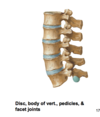

two main segments of the typical vertebrae

arch and body

how many processes are there?

what if you include the mammillary processes?

7 processes; but 9 total if you count the mammillary processes

what are the 7 articular processes on the vertebrae?

1 spinous process

2 transverse processes,

4 articular processes (=2 superior/2 inferior)

which processes “arise from junction of pedicles & laminae, except for L5”

transverse process

how do transverse processes change in the lumbar region?

From L1-L3:increasein size fromL1-L3, whereas

L4/L5: decrease in size of transverse processes